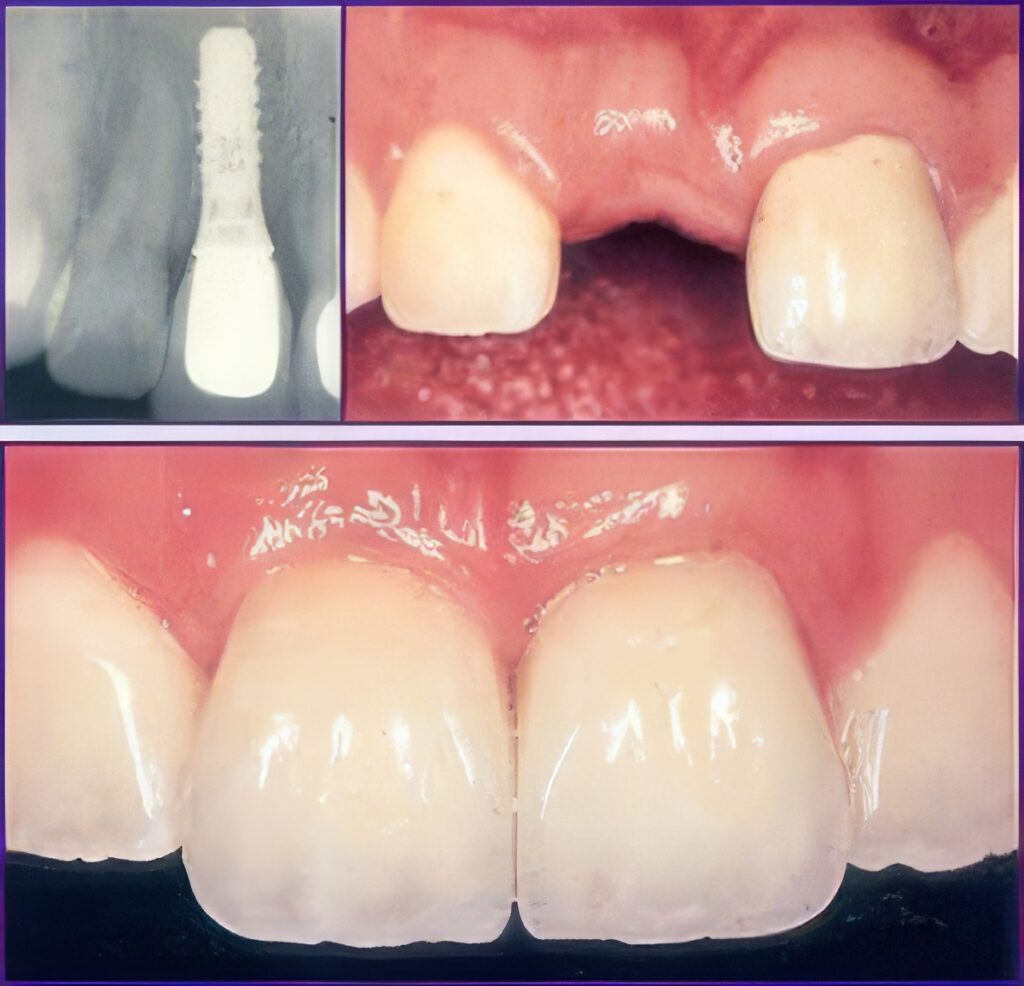

The procedure starts with developing a treatment plan to match your needs. Then an artificial root, which is a tiny post made of titanium, is installed in your jawbone. It takes 6 to 12 weeks for the bone to heal, and after that an abutment (a small connector post) is attached to securely hold the needed dental prosthesis.

The principal purpose of a dental implant is to serve as a solid base for fixed or removable prosthetic teeth. However, there are quite a few advantages for getting dental implants Sherman. As they look and feel like a natural tooth does, an artificial root gives you the chance to smile with confidence, in turn, boosts your self-confidence.